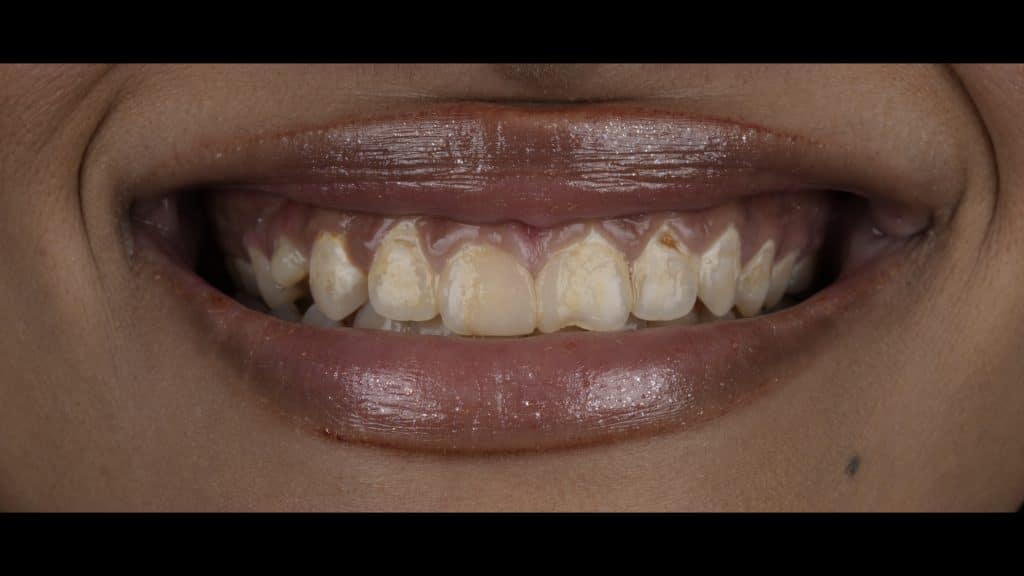

The before picture

she obviously don't brush her teeth, all her anteriors are square in shape due to the gum problems she have.

The teeth need treatment and the gum need to be healthy and correct

she don't have shifting in midline